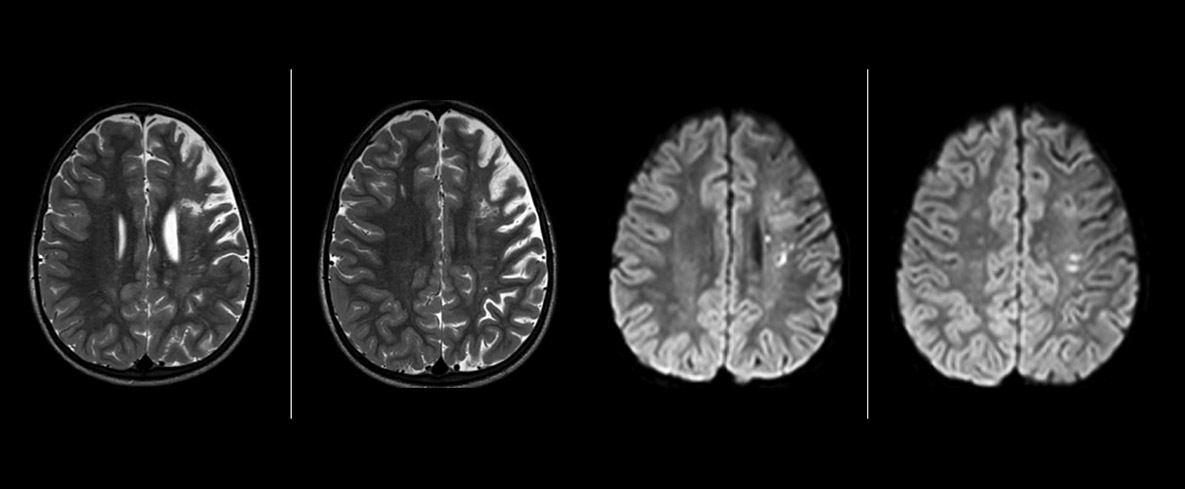

Philips mDIXON TSE is a two-point DIXON technique that separates water and fat signals, for time-efficient fat-free imaging, even in challenging neuro anatomy. “mDIXON TSE has been one of the most significant improvements in imaging sequences that we have utilized to date at PCH,” says Dr. Miller. “Its multi-parametric acquisition allows us to obtain fat suppressed images and equivalent non-fat suppressed T2 images all in the same sequence. In addition, prior methods of fat suppression could be artifactually corrupted by poor patient anatomy or poor operator application, but with mDIXON we now have a robust and reliable method of fat suppression.” Fat saturation is historically challenging at the ends of fields of view, especially in total spine imaging and in difficult patient anatomy such as the lower regions of the neck. “Due to the unique fat suppression capabilities of mDIXON, however, these challenges no long apply,” says Dr. Miller. “We routinely obtain homogeneous fat suppression under virtually all conditions. It has also led to some efficiencies by not having to repeat sequences because of that technical failure.”

“mDIXON TSE has increased our diagnostic confidence in ruling in or ruling out abnormalities in which fat suppression is critical to diagnosis, such as metastatic disease or osseous abnormalities.”

“mDIXON TSE is most useful in patients with lesions or abnormalities in the soft tissues such as the face and neck, and for patients with contrast enhancing abnormalities that are mostly visible with fat suppression,” says Dr. Miller. “All our spine imaging now routinely contains mDIXON water-only T2 images, and this allows us to identify pathology that may be obscured by non-fat suppressed imaging such as injuries of the bone. And it’s not necessary to obtain additional standard TSE T2 images because the in-phase mDIXON images are equivalent to standard TSE T2 images.”